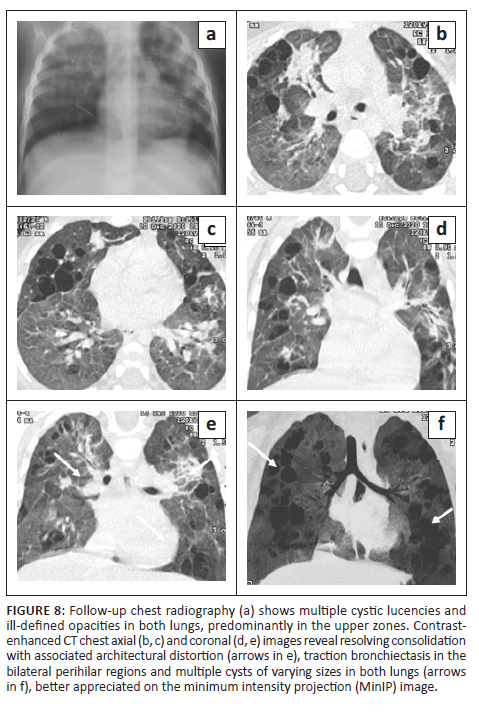

An 18-month-old male with disseminated MDR TB, on an MDR regimen for 5 months, with severe acute malnutrition and recurrent pneumothoraces was being followed up. The patient had a history of a recent admission with a right-sided pneumothorax (Figure 7) and pneumonia. He was managed with ICD tube drainage and IV antibiotics and subsequently discharged. A follow-up CXR (Figure 8) after 2 months showed multiple cystic lucencies and haziness in both lungs, predominantly in the upper zones. The CT chest (Figure 8) revealed resolving consolidation with associated architectural distortion and traction bronchiectasis in the perihilar regions along with multiple cysts of varying sizes in both lungs. The patient responded to ATT (MDR regimen) and subsequently recovered.